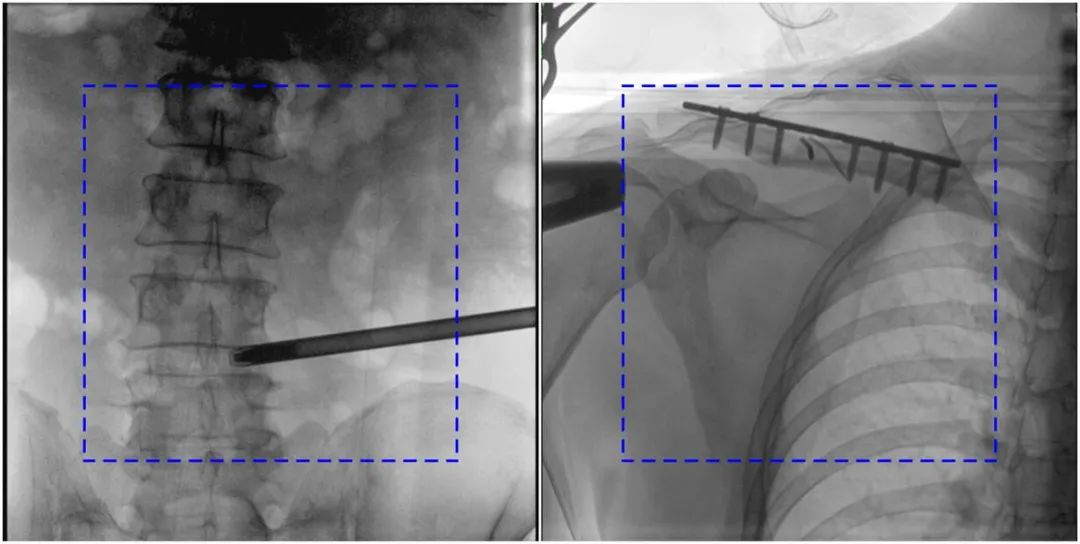

PLX119C臨床圖像與傳統圖像對比

注:藍色虛線內為傳統21CM×21CM平板的成像區域。